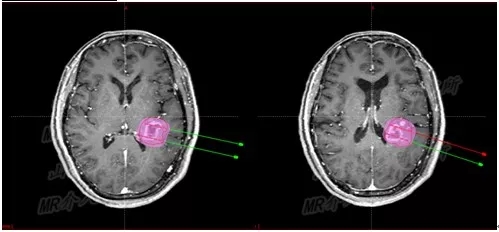

3D打印模板术中定位

但是磁共振+3D打印模板+I125粒子植入的创新组合,却是史无前例。

根据满女士的治疗计划,李成利主任找专人制作了颅脑介入手术专用的3D打印引导模板。

介入手术治疗中,

磁共振实时引导技术保证介入手术过程在可视化下连续性完成

手术过程仅半小时,先对满女士进行局麻,然后在1.0T开放式介入磁共振监控及3D打印模板引导下,

李成利主任将4根磁共振兼容性穿刺针平行穿刺至肿瘤病变既定位置,根据近距离放疗计划植入I125放射性粒子,

该粒子通过持续释放低剂量γ射线对肿瘤细胞起到杀伤作用,而且对周边正常脑组织损伤较小。